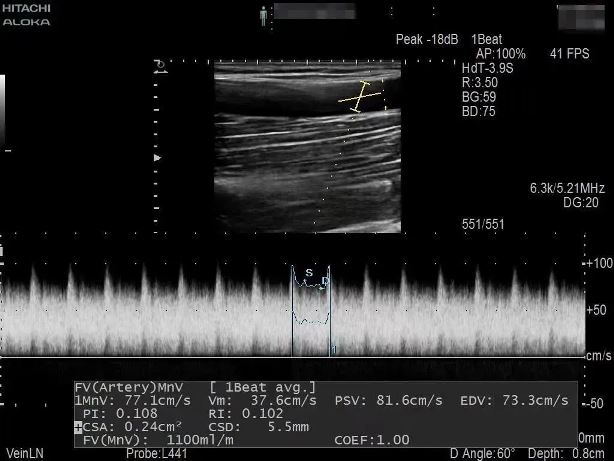

患者1年前出現(xiàn)周身乏力伴有雙下肢水腫癥狀,在外院行“為腎透析的動(dòng)靜脈造瘺術(shù)”后規(guī)律透析治療。因內(nèi)瘺無(wú)震顫2日,為求系統(tǒng)治療來(lái)院,入院后腎內(nèi)科金明花主任帶領(lǐng)醫(yī)護(hù)團(tuán)隊(duì)立即完善相關(guān)檢查,診斷為:動(dòng)靜脈內(nèi)瘺血栓形成,經(jīng)超聲檢查發(fā)現(xiàn)動(dòng)靜脈內(nèi)瘺血栓形成狹窄,最窄處內(nèi)徑約1.6mm。

為了節(jié)約患者有限的血管資源,盡早治療,經(jīng)過(guò)腎病內(nèi)科金明花主任及科室共同討論并爭(zhēng)得患者家屬同意后,決定對(duì)患者進(jìn)行超聲引導(dǎo)下動(dòng)靜脈內(nèi)瘺球囊擴(kuò)張術(shù)+血栓碎栓術(shù)解決內(nèi)瘺狹窄及血栓。手術(shù)過(guò)程中金明花主任在內(nèi)瘺狹窄位置近心端進(jìn)行穿刺,沿穿刺針置入導(dǎo)絲、置入血管鞘,在超聲實(shí)時(shí)引導(dǎo)下球囊到達(dá)病變部位,緩慢擴(kuò)張球囊,解決狹窄病變,并壓碎血栓,使內(nèi)瘺通暢。整個(gè)手術(shù)僅用30分鐘,用時(shí)少,效果明顯,術(shù)后內(nèi)瘺血管雜音及震顫明顯,手術(shù)效果立竿見(jiàn)影。